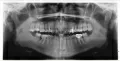

Все ли в порядке с моими зубами?

• На нижней челюсти справа отсутствует 6-ой зуб, нужно замещать дефект. 5-ке слева нужно восстановить коронковую часть. 8-ой зуб полуретинированый показан удалению, наклонён в дистальную стенку 7-ого зуба и возможно смещение зубов.